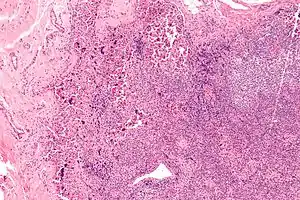

| Lymphadenopathy due to systemic lupus erythematosus with characteristic necrosis and haematoxylin bodies. H&E stain. | |